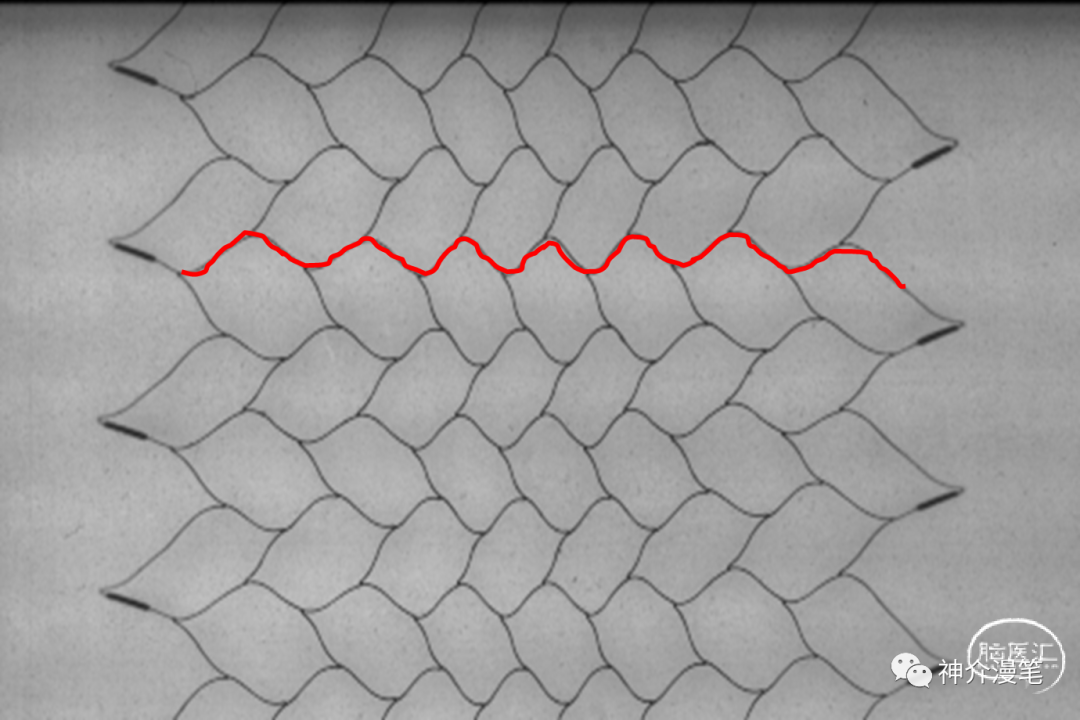

闭环支架的设计特点和开环支架刚好相反,所有的支架单元都呈现出连续封闭的状态,整个支架为一个连续完成的整体。其设计的特点使得其网眼更小,更利于提高局部金属覆盖率与对斑块的保护。但是其在迂曲血管的贴壁性会略差,同时因为其作为一个整体存在的特点,其趋势是使血管变直。因此对于血管走形的改变会略大。下图为闭环支架的设计特点,可以看到所有支架网格均为封闭连续的结构。

闭环支架更大的优势来源于更密更为紧凑的网孔设计,对于提高局部金属覆盖率,保护斑块脱落,特别是溃疡斑块,软斑块等有其独特的优势。此外对于串联病变,闭环支架具备更好的二次通过性,内壁更为光滑,很少出现导管通过困难等问题。因此对于对于串联病变,夹层修复,编织闭环更具优势。

波科 WALLSTENT 支架

Wallstent支架不同于前面两款,自身特点同样突出,关键词:编织支架,闭环支架,自膨支架,是目前主流颈动脉支架中唯一一款编织支架。具备着编织支架普遍共性,在不同管径血管内会被拉伸和短缩,释放难度略高于其他几款支架,但是有更高的金属覆盖率和更小的网眼面积。此外,wallstent支架的显影性是最棒的,这一点用过的可能都知道。

而对于串联病变,需要更好的支架释放后的通过性能,进行远端操作时,闭环支架就有明显的优势。内壁更为光滑,中间导管或通路导管通过会更加便利。

除外串联病变,起始处高负荷斑块,不稳定斑块,夹层修复,使用Wallstent可能有更好近端斑块覆盖能力及修复能力。